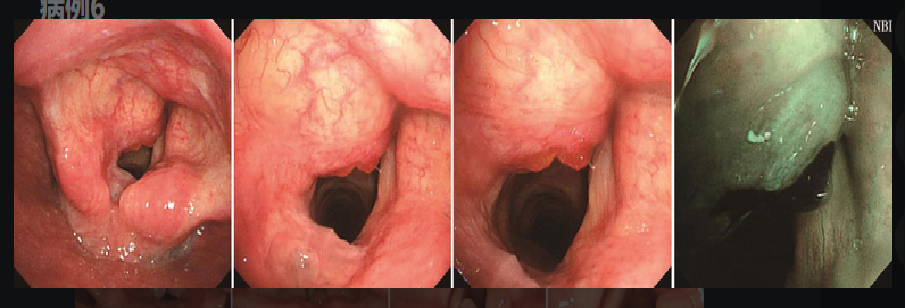

声带息肉

A.左侧声带前中1/3交界处游离缘可见无蒂息肉样突起,大小约3mm;

B.NBI模式下息肉表面未见异常的扩张血管(Ⅰ型);

C.活检钳贴近声带息肉表面,准备咬取;

D.活检钳垂直咬取息肉;

E.活检钳将息肉摘除;

F.声带息肉摘除后表现,黏膜有出血,声带表面基本变平整。